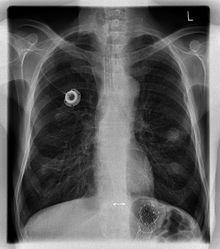

The port is usually inserted in the upper chest (known as a "chest port"), just below the clavicle or collar bone, with the catheter inserted into the jugular vein.

A port consists of a reservoir compartment (the portal) that has a silicone bubble for needle insertion (the septum), with an attached plastic tube (the catheter). The device is surgically inserted under the skin in the upper chest or in the arm and appears as a bump under the skin. It requires no special maintenance other than occasional flushing to keep clear. It is completely internal so swimming and bathing are not a problem. The catheter runs from the portal and is surgically inserted into a vein (usually the jugular vein or less optimally the subclavian vein). Ideally, the catheter terminates in the superior vena cava or the right atrium. This position allows infused agents to be spread throughout the body quickly and efficiently.

A follow-up chest radiograph can immediately detect complications associated with the procedure in the form of pneumothorax, hemothorax and malpositions of the catheter (see Risks below for further details). However, it is suggested that chest radiography is not mandatory as a routine method after fluoroscopy-guided port insertion that is mainly performed by venous cutdown.[3]

Ports can be put in the upper chest or arm. The exact positioning itself is variable as it can be inserted to avoid visibility when wearing low cut shirts, and to avoid excess contact due to a backpack or bra strap. The most common placement is on the upper right portion of the chest, with the catheter itself looping through the right jugular vein, and down towards the patient's heart.